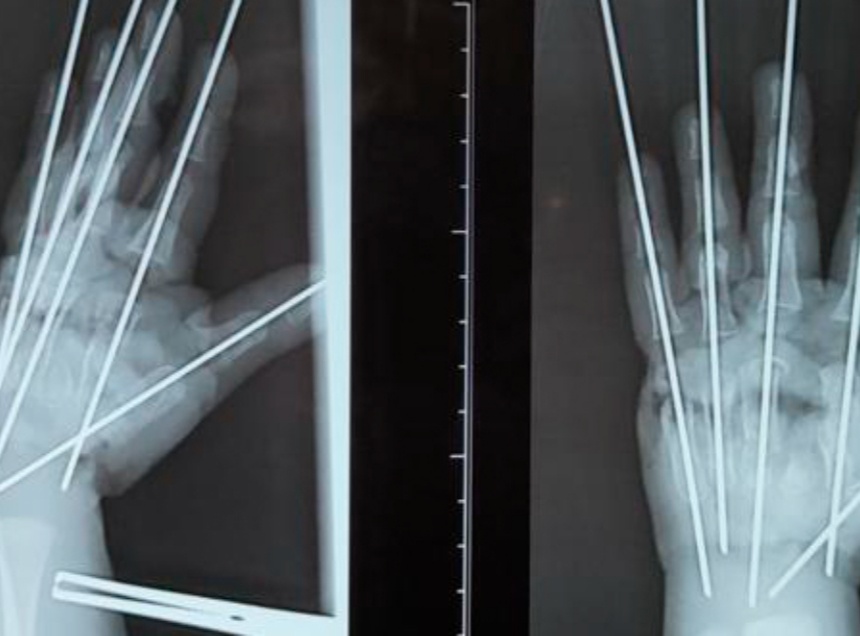

По словам врача, из-за раздавливающего механизма мясорубки травма у ребенка была тяжелой. У мальчика были раздроблены кости, сосуды, сухожилия, нервы – повреждена была вся кисть. «Фактически имела место ампутация – кисть держалась на нескольких связках. Нашей задачей было сохранить жизнеспособные ткани, восстановить анатомию конечности и кровообращение», – подчеркнул Антон Волков.

Травмированную руку в ходе операции собрали буквально по частям. Сначала врачи выполнили металлоостеосинтез для соединения осколков костей. «Затем было необходимо восстановить кровоснабжение кисти», – отметил микрохирург.

В ходе операции юному псковичу также потребовалась аутовенозная пластика, в рамках которой фрагментом подкожной вены пациента был замещен размозженный участок локтевой артерии. После этого пальцы мальчика начали понемногу розоветь.